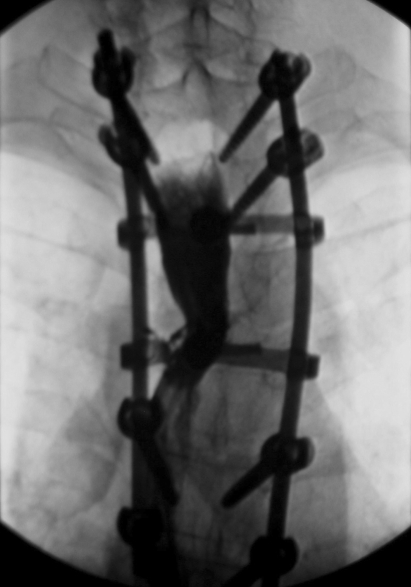

Fig. 4.

Oesophageal contrast study demonstrating the presence of a leak in the oesophagus at the level of the fractured vertebrae